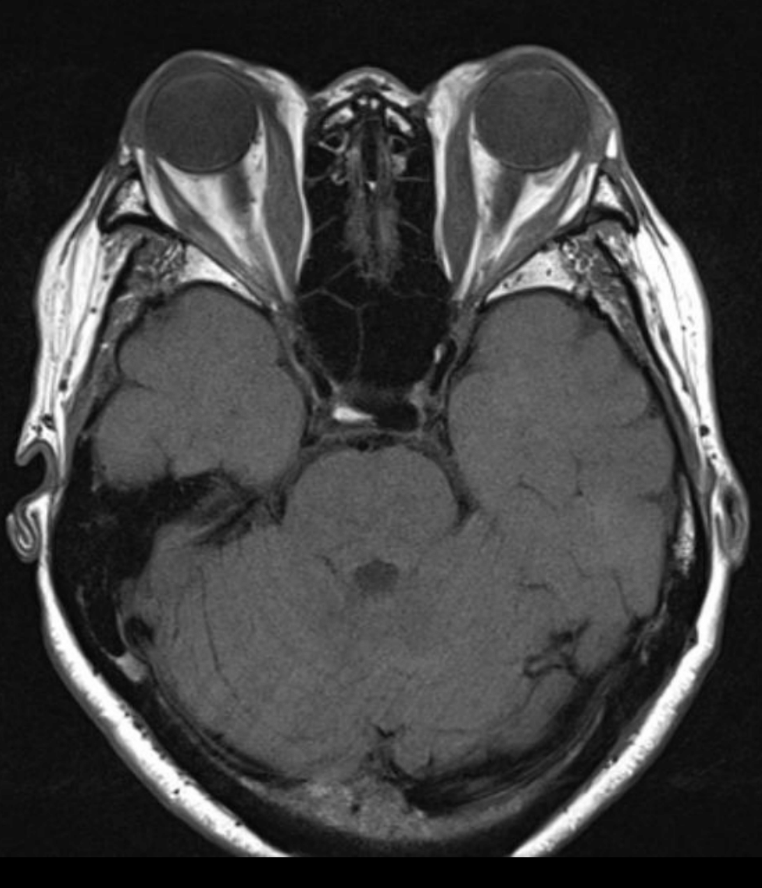

¿Cómo vemos los músculos en fase aguda de Graves, en secuencia T2 ?

Con aumento de señal

¿Cómo vemos los músculos en fase crónica de Graves, en secuencia T2 ?

Con disminución de señal

Diagnóstico

Graves